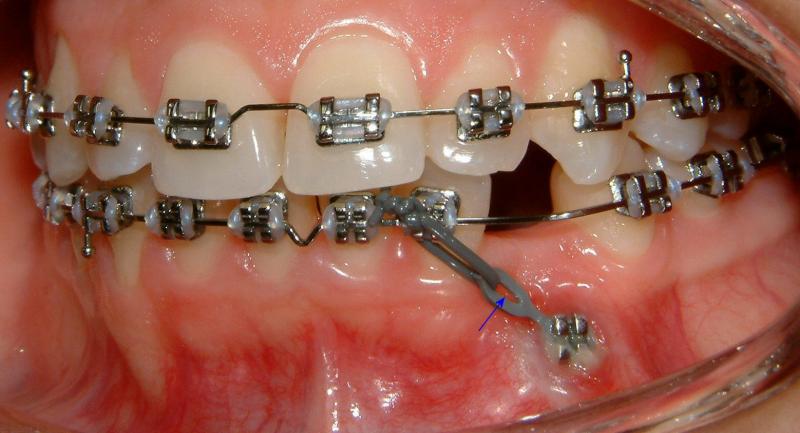

In the 2nd post-op visit (2 weeks after the surgery), the pulling is activated. The force exerted in pulling can be estimated from the shape of the hole of the color tie (Fig. 21). It deforms from a perfect circle (unstretched) to an approximated ellipse (stretched); shown by the blue arrow. The figure also shows improved healing.

Fig. 21 Second post-op visit, 2 weeks after surgical exposure; activated pulling (progress, improved healing)© Copyright 2007-2014, Vu Orthodontics. All rights reserved.